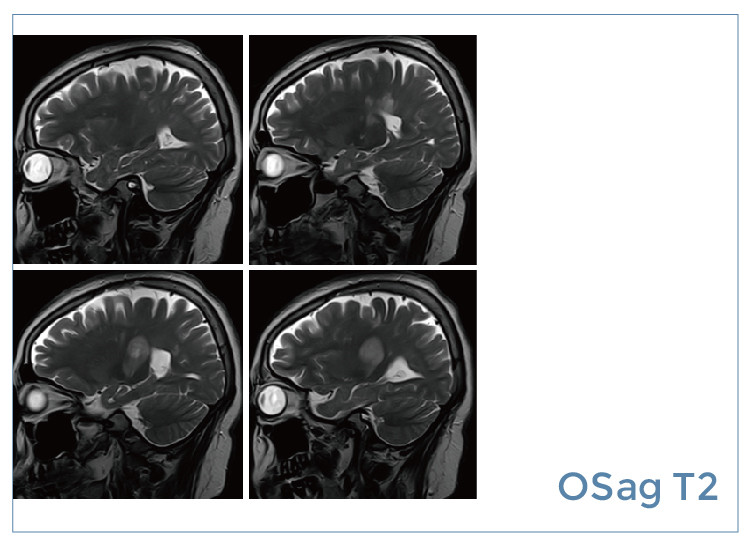

【朗润影像档案】磁共振影像病例分享(编号20190823)